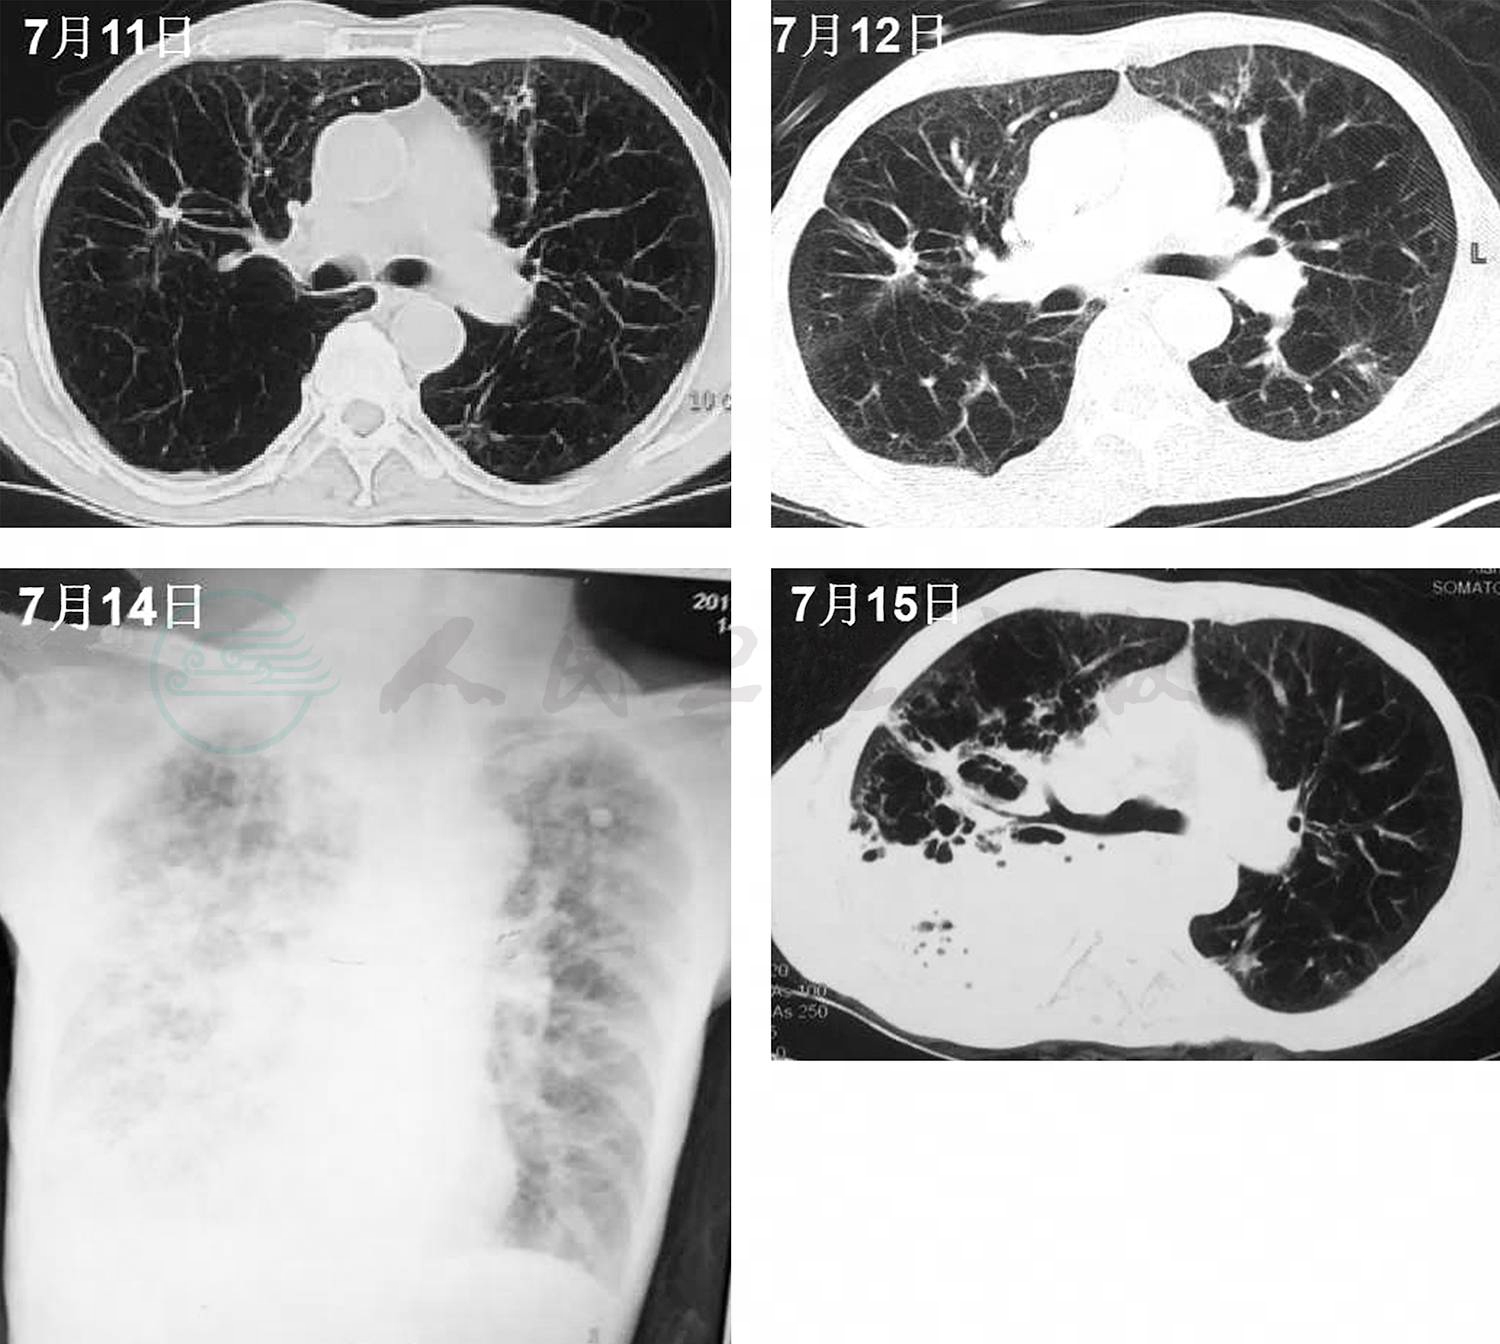

9.胸部CT 双肺多发纤维条索结节影,少许斑片渗出病灶;肺气肿;双侧胸膜增厚、粘连(图1)。

图1 肺部 CT(2017年7月11日)